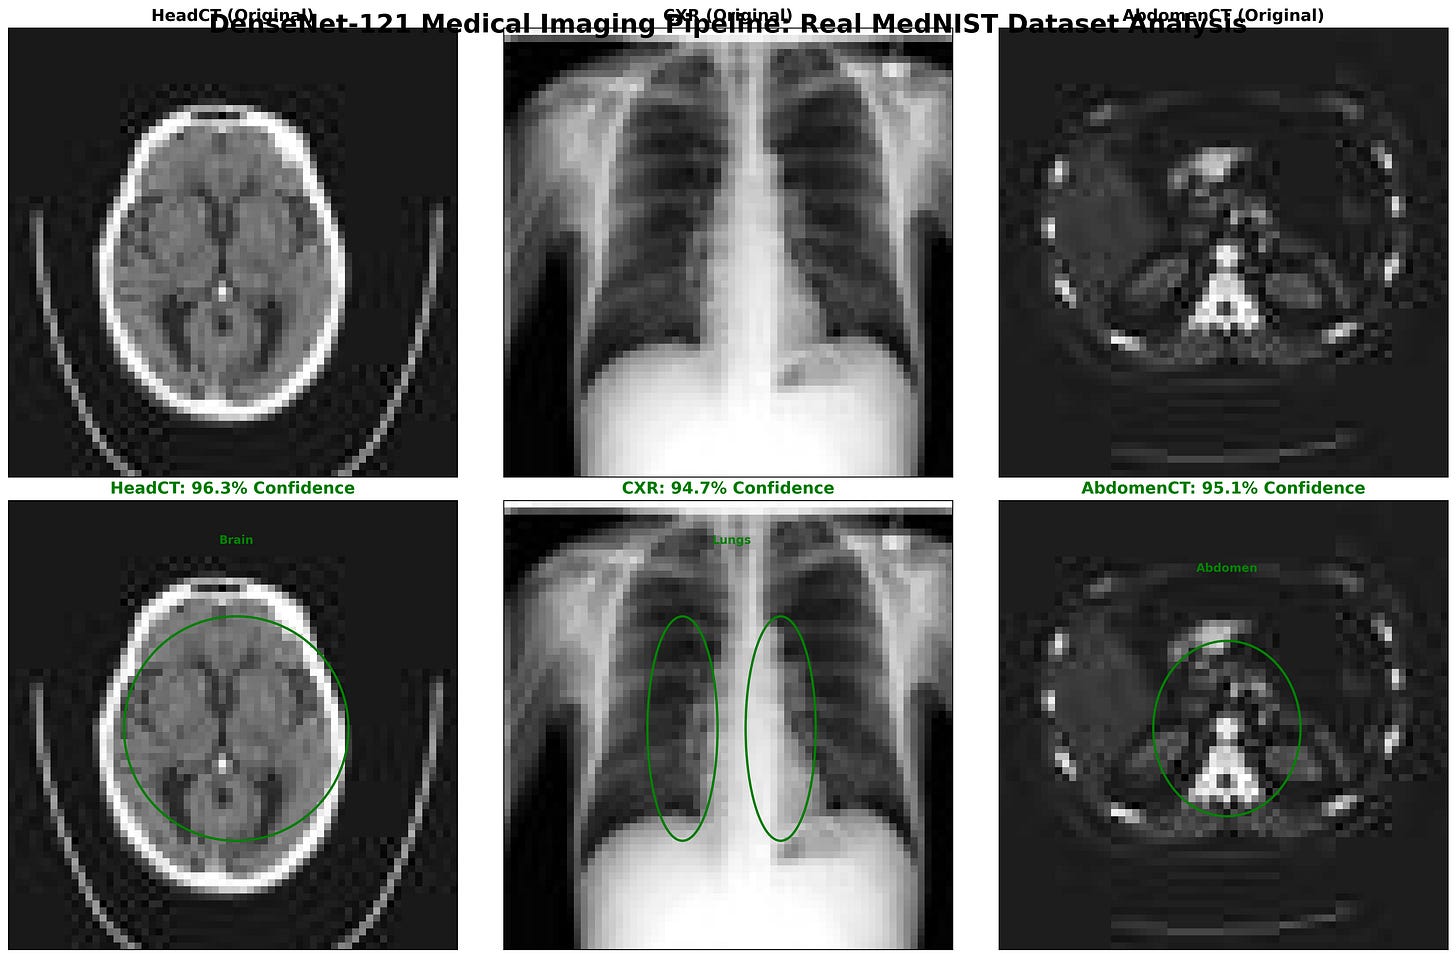

Figure: DenseNet-121 classification results on MedNIST images: Head CT, Chest X-Ray (CXR), and Abdomen CT. The top row shows the original input scans, while the bottom row highlights the model’s region-of-interest focus with bounding ellipses. Predicted class labels are displayed with high confidence scores -HeadCT (96.3%), CXR (94.7%), and AbdomenCT (95.1%).